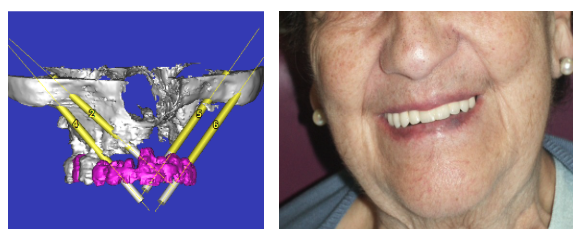

Paciente con atrofia total del maxilar, resuelta con Implantes ZIGOMÁTICOS y 1 implante anterior. Planificación informática y Modelos 3D

Imagen de la rx con los implantes colocados, e imagen de la prótesis acrílica.